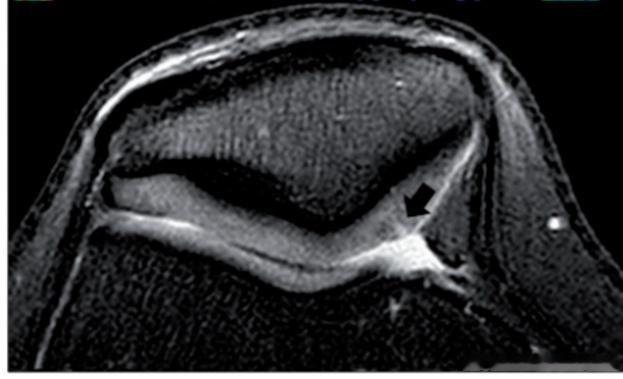

三级(图4):MRI显示关节软骨深度>50%,未达骨质层,软骨层出现高信号的形态(同上,程度深)

——症状:涉及运动过程中的不适或疼痛。

四级(图5):MRI显示全层软骨缺失,伴有下方骨反应性改变

——症状:活动疼痛,导致活动能力下降。